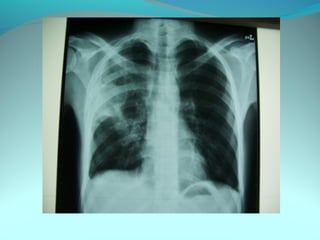

Clarté retroclaviculaire gauche d 3cm de diam

entouré d’une paroi de 1cm d’epaisseur

La limite interne se confend avec le mediastin

Les autre limites sont nette

DIAGNOSTIC

Caverne tuberculeuse gauche